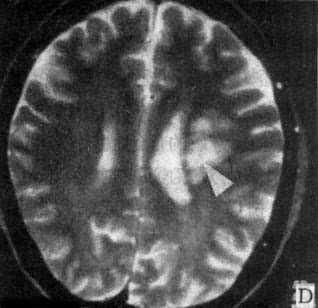

MRI 适宜于观察CT扫描为等密度的亚急性脑内血肿,已如前述。脑梗塞的发现MRI比CT扫描要早,一般起病后6小时MRI即可出现异常。脑干和小脑腔隙性梗塞灶的探测,MRI明显优于CT。脑梗塞灶在T1WI上呈低信号,在T2WI上呈高信号(图5-1-6C、D)。

图5-1-6 MRI扫描SE序列图像

在矢状面(A)和冠状面(B)T1WI可见垂体肿块向鞍上延伸,呈等信号区(→);在横断面T1WI(C)和T2WI(D)上分别可见左枕和右基底节区脑梗塞灶呈低和高信号区(→);在矢状面T1WI(E)和横断面T2WI(F)上,可见基底动脉瘤环形影,其内为低信号和高信号区,高信号区为瘤内血栓形成(→)